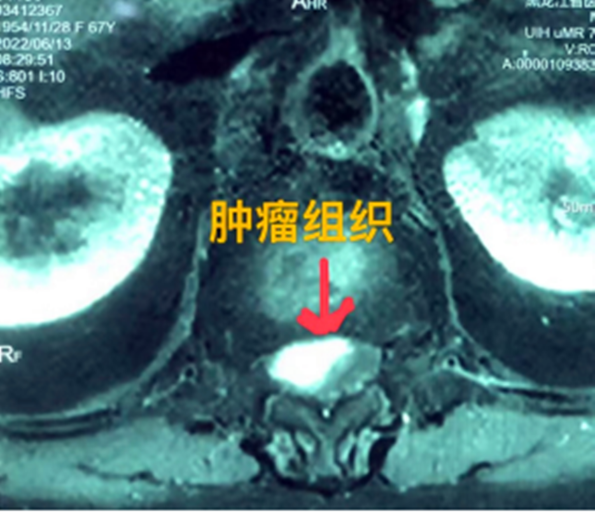

據(jù)省醫(yī)院神經(jīng)外一科陶宇醫(yī)生介紹,家住外地的張大娘最近總感覺雙下肢疼痛、無力,且排尿困難及便秘,伴有行走困難。時間長了,張大娘病情逐漸加重,劇烈的疼痛甚至讓她無法完整入睡。在當?shù)蒯t(yī)院,張大娘按腰椎肩盤突出接受治療,但未見好轉,隨后進行的胸椎MRI(核磁共振)檢查,結果不禁讓張大娘和家屬瞠目結舌,原來張大娘患的竟然是少見的脊髓腫瘤。

張大娘住進了黑龍江省醫(yī)院神經(jīng)外一科,該科孫國章主任醫(yī)師熱情地接待了張大娘,并邀請骨外一科專家共同為她進行了聯(lián)合會診。發(fā)現(xiàn)張大娘病情十分復雜棘手,脊髓腫瘤體積較大,充滿髓腔且神經(jīng)已經(jīng)完全受壓,需要手術來完整切除。同時還發(fā)現(xiàn)張大娘的胸腰部曾受過兩次外傷,伴有多處骨折,這對接下來的手術操作帶來一定影響。